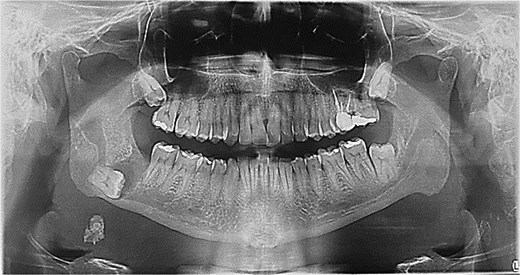

A 49-year-old male patient was referred, after a radiographic finding in a panoramic radiography, for evaluation of the lower right third molar (48) in an ectopic position associated with a radiolucent image, which suggested a cystic lesion (Fig. 1). A cone-beam computed tomography was made. The 3D imaging exams showed the presence of tooth 48 in the mandibular base, in the right angle region, associated with the radiolucent image, lingual fenestration, and intimate relationship between the third molar and the mandibular canal (Fig. 2). Due to the dental position, to have better visualization and less morbidity a submandibular extraoral approach was planned. The tooth removal and cyst curettage were made through the Risdon approach (Fig. 3). A fixation system with reconstruction plate (2.4 mm) was used to prevent a mandibular pathological fracture (Fig. 4). Anatomopathological examination of the cystic capsule was performed with a diagnosis of dentigerous cyst. In the postoperative period, the patient reported alteration in the sensitivity of the inferior alveolar nerve. Postoperative radiographic examinations showed adequate adaptation of the fixation system and complete surgical removal of the tooth and associated lesion. Orthopantomography with 4 months follow-up showed bone repair and adequate adaptation of the fixation system (Fig. 5).

The ectopic third molar usually is asymptomatic and difficult to identify. However, the clinical symptoms include swelling, limited mouth opening, pain, discharging fistula, or temporomandibular joint discomfort [4, 6, 10]. The diagnosis of ectopic third molar is completely formed with radiographic findings such as panoramic radiograph or computerized tomography, that performs 3-dimensional information and precise location of the ectopic tooth and surrounding structures [5, 11]. The panoramic radiography showed the location of the third molar in the present case, but only after the cone-beam tomography examination the treatment plan was defined. The lingual position, the close relationship with the mandibular canal and the caudal position determined the removal through the submandibular approach.